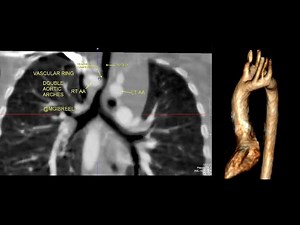

1 year child with stridor CT shows complete vascular ring , DAA ; Do

…

已浏览 1325 次

2021年12月27日

YouTube

Cardiac Imaging M.Gibreel